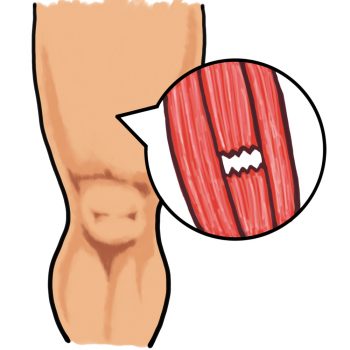

■ 捻挫や肉離れ、打撲…意外と多い「日常のケガ」

スポーツをしている方だけでなく、

日常生活の中でもケガは意外と多く起こります。

・段差で足をひねった

・急に走ってふくらはぎを痛めた

・家具にぶつけて強く打った

こうした

捻挫・肉離れ・打撲 は、整骨院でよく相談されるケガです。

■ ケガの直後は「炎症」をどう抑えるかが大事

捻挫や肉離れ、打撲などの外傷では、

まず炎症が起こります。

■ 放置するとケガは「クセ」になる

捻挫を繰り返す人がいるのはなぜでしょうか。

理由の一つは、

関節の安定性が戻っていない状態で日常生活に戻ってしまうこと。